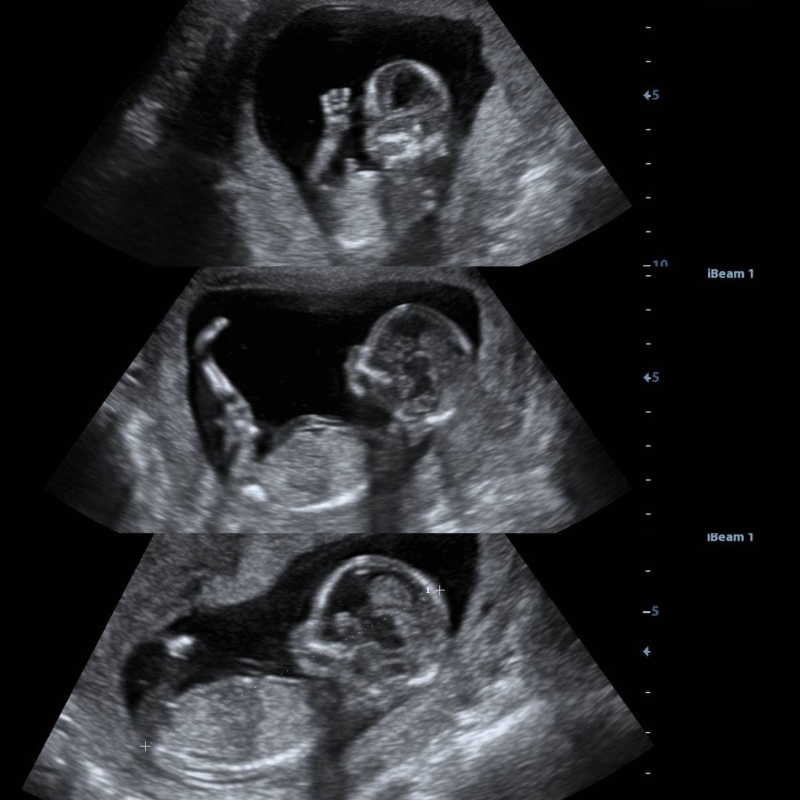

2D pretecho

Tweedimensionaal bewegende beelden van je baby in zwart-wit